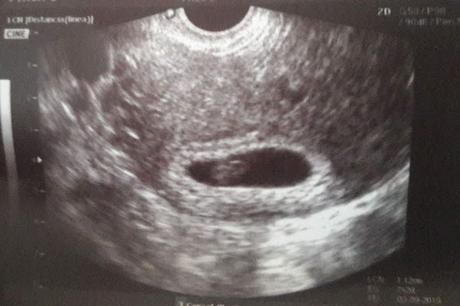

Ecografía de la semana 12

Hasta el 17 no vi a mi ginecóloga y con una primera ecografía se confirmó el embarazo. Estaba de 7 semanas.

Ecografía en la semana 7

En cuanto a las pruebas que me he hecho han sido varias ecografías y un primer análisis donde salió baja la vitamina D, aunque la más importante es la de la semana 12, en la que ven el pliegue nucal, donde junto a un análisis de sangre (cribado) descartan posibles problemas cromosómicos (el 21 y el 18); yo tenía un poco de miedo por mi edad (este año cumplo 37), pero me salió un riesgo bastante bajo, por lo que se descartó realizar la anmiocentesis.